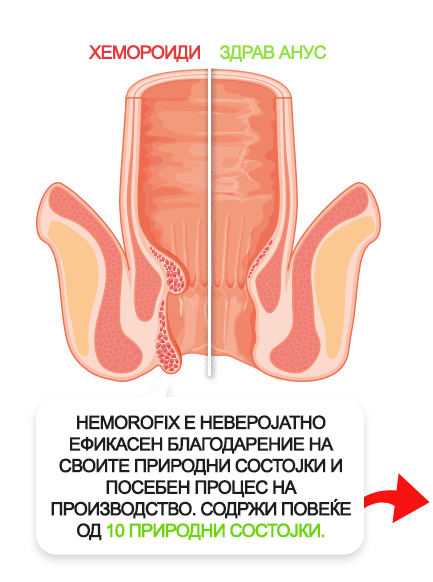

КАКО ХЕМОРОФИКС ГИ ЕЛИМИНИРА ХЕМОРОИДИТЕ?

Природните супстанции во Хеморофикс ги намалуваат симптомите на хемороиди по само една употреба.

- 100% природни состојки ја елиминираат болката, печењето и чешањето

- Крвните садови се стеснуваат за 5 пати, а крвавењето престанува

- Пропустливоста на вените се намалува, а тие стануваат за 130% поеластични

- Згрутчувањата во крвните садови се елиминираат, а дефекацијата конечно станува полесна

ДО ШТО МОЖАТ ДА ДОВЕДАТ ХЕМОРОИДИТЕ?

Фекална инконтиненција

Тромбоза на хемороидалните јазли со локална некроза на ткивото

Венозна стаза во патолошки изменети проширени вени

Крвавење од потслизестите крвни садови, што доведува до некроза на ткивото и анемија

Ректален карцином